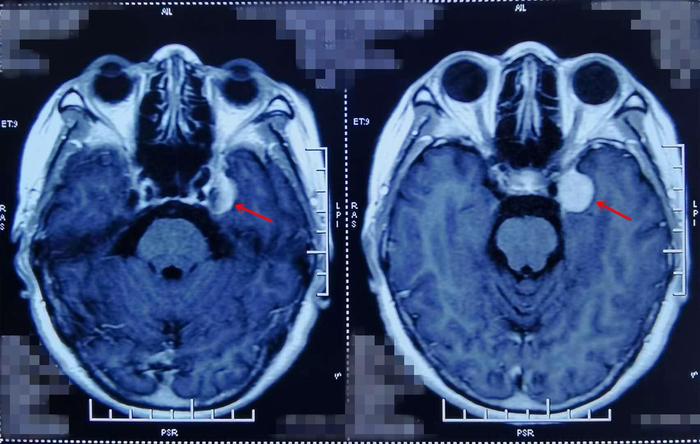

术前影像学资料

“从刘阿姨核磁检查上来看,肿瘤并不算太大,但是位置很特殊,周围多是神经与血管,这给手术增加了难度。不过你们也不要担心,这类手术在我们这里是很常规的手术,你们从银川远道而来,这是对我们最大的信任,我也得让你们放心,让刘阿姨健健康康的回家!”门诊中,张治国教授耐心细致的为刘阿姨和女儿分析着病情。

完善各项术前准备后,刘阿姨被推进了手术室,张治国教授亲自为刘阿姨做手术。肿瘤基底从蝶骨嵴向海绵窦壁、岩骨生长,凭借20多年的从医经验,再加上准确精细的手术操作,张治国教授通过颞下入路手术切除肿瘤后,可以看见动眼神经、颈内动脉、小脑幕保护的很好,同时颞叶脑组织和回流静脉也完好无损,手术非常成功!